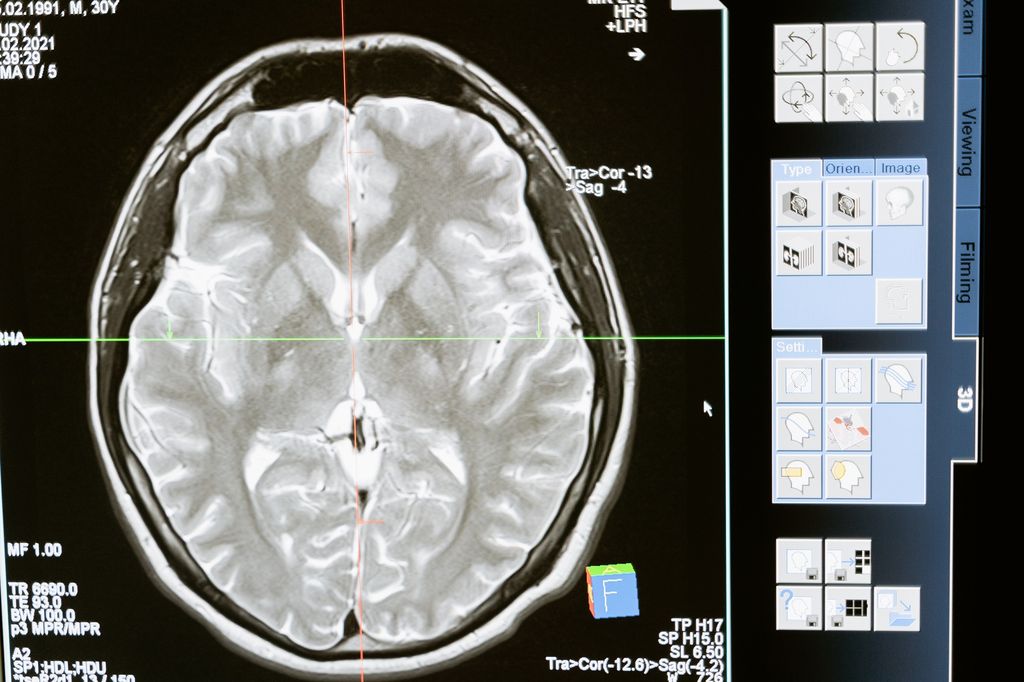

Otak merupakan organ vital pada tubuh manusia dan makhluk hidup lainnya. Terdiri dari beberapa bagian, otak memiliki tugas dan fungsi masing-masing yang banyak untuk mendukung keberlangsungan hidup.

Diketahui ada empat bagian otak pada manusia, yaitu cerebrum, cerebellum, brainstem, dan neuron. Ketiganya memegang peranan penting dan besar. Bisa dibilang bahwa otak adalah pusat dari organ tubuh lainnya, seperti mengontrol semua fungsi tubuh dan menafsirkan informasi dari dunia luar.

Bagian Otak Manusia

Cerebrum adalah bagian otak terbesar dalam susunannya yang kompeks. Dikutip dari My Field Clinic, cerebrum terdiri dari bagian kanan dan kiri. Fungsi otak ini adalah melakukan fungsi besar seperti mengartikan sentuhan, penglihatan dan pendengaran, ucapan, penalaran, emosi, pembelajaran, dan kontrol gerakan yang baik.

Kemudian ada cerebellum atau otak kecil yang terletak di bawah cerebrumFungsi otak bagian ini adalah untuk mengkoordinasikan gerakan otot, termasuk keterampilan motorik seperti keseimbangan, koordinasi, dan postur.

Sementara itu bagian batak otak atau brainstem adalah bagian otak yang berfungsi sebagai pusat relay. Ia menghubungkan otak besar dan otak kecil ke sumsum tulang belakang, yang menjalankan banyak fungsi otomatis seperti pernapasan, detak jantung, suhu tubuh, siklus bangun dan tidur, pencernaan, bersin, batuk, muntah, dan menelan.

Sedangkan neuron adalah struktur sistem syaraf pusat yang berfungsi sebagai pengirim dan membawa informasi. Bagian ini memungkinkan berbagai bagian otak untuk berkomunikasi satu sama lain, serta memungkinkan otak untuk berkomunikasi dengan berbagai bagian tubuh.

Dikutip dari Very Well Mind, peneliti memperkirakan ada sekitar 86 miliar neuron di otak manusia. Amazing!

Ukuran Otak Manusia

Menjadi pusat semesta kehidupan manusia, pernah terpikirkan, nggak, sih, berapa ukuran otak yang kamu miliki? Dihimpun dari Very Well Mind, otak manusia memiliki struktur yang mirip dengan mamalia lain. Namun, yang membedakannya adalah ukurannya berdasarkan berat badan.

Soal berat, otak manusia dewasa memiliki berat rata-rata 1300--1400 gram atau 1,3--1,4 kilogram. Sedangkan panjangnya, otak orang dewasa rata-rata memiliki panjang sekitar 15 sentimeter.

Sebagai perbandingan, bayi manusia yang baru lahir, biasanya memiliki berat sekitar 350-400 gram. Sedangkan pria cenderung memiliki otak yang lebih besar daripada perempuan.

Umumnya, setelah memperhitungkan berat badan secara keseluruhan, pria punya otak cenderung lebih besar sekitar 100 gram daripada otak perempuan. Lebih lanjut, bagian lobus frontal dan korteks limbik, yaitu area yang berfungsi dalam pemecahan masalah dan regulasi emosi, cenderung lebih besar daripada punya pria.

Sebaliknya, otak pria punya korteks parietal, yaitu lapisan yang berfungsi untuk memproses informasi sensorik dari panca indra, dan bagian amigdala atau bagian yang memproses memori dan respons emosional, cenderung lebih besar daripada perempuan.